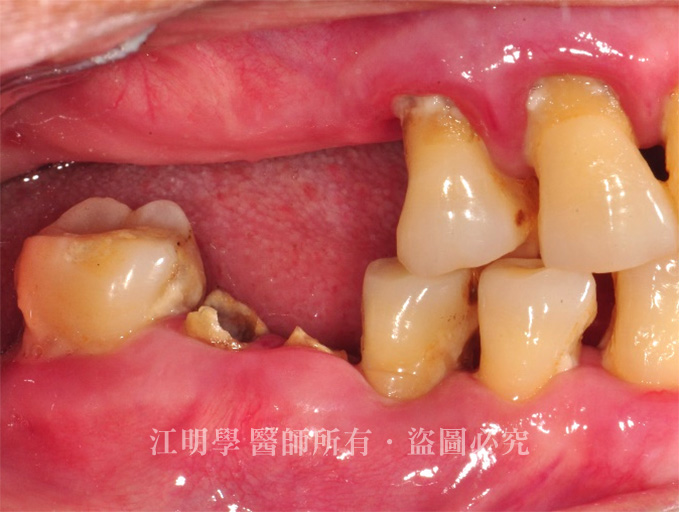

治療前

治療前:後牙多處缺牙導致咀嚼困難

後牙有多處缺牙,飲食上只能吃軟食,大笑時又會看到缺牙區,因為害怕看牙醫,拖延治療導致多處缺牙、牙周病問題嚴重。